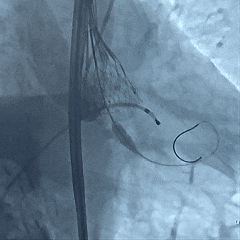

右冠造影

左冠造影

主动脉根部造影,瓣叶活动度差

20mm球囊扩张,轻微腰征无漏